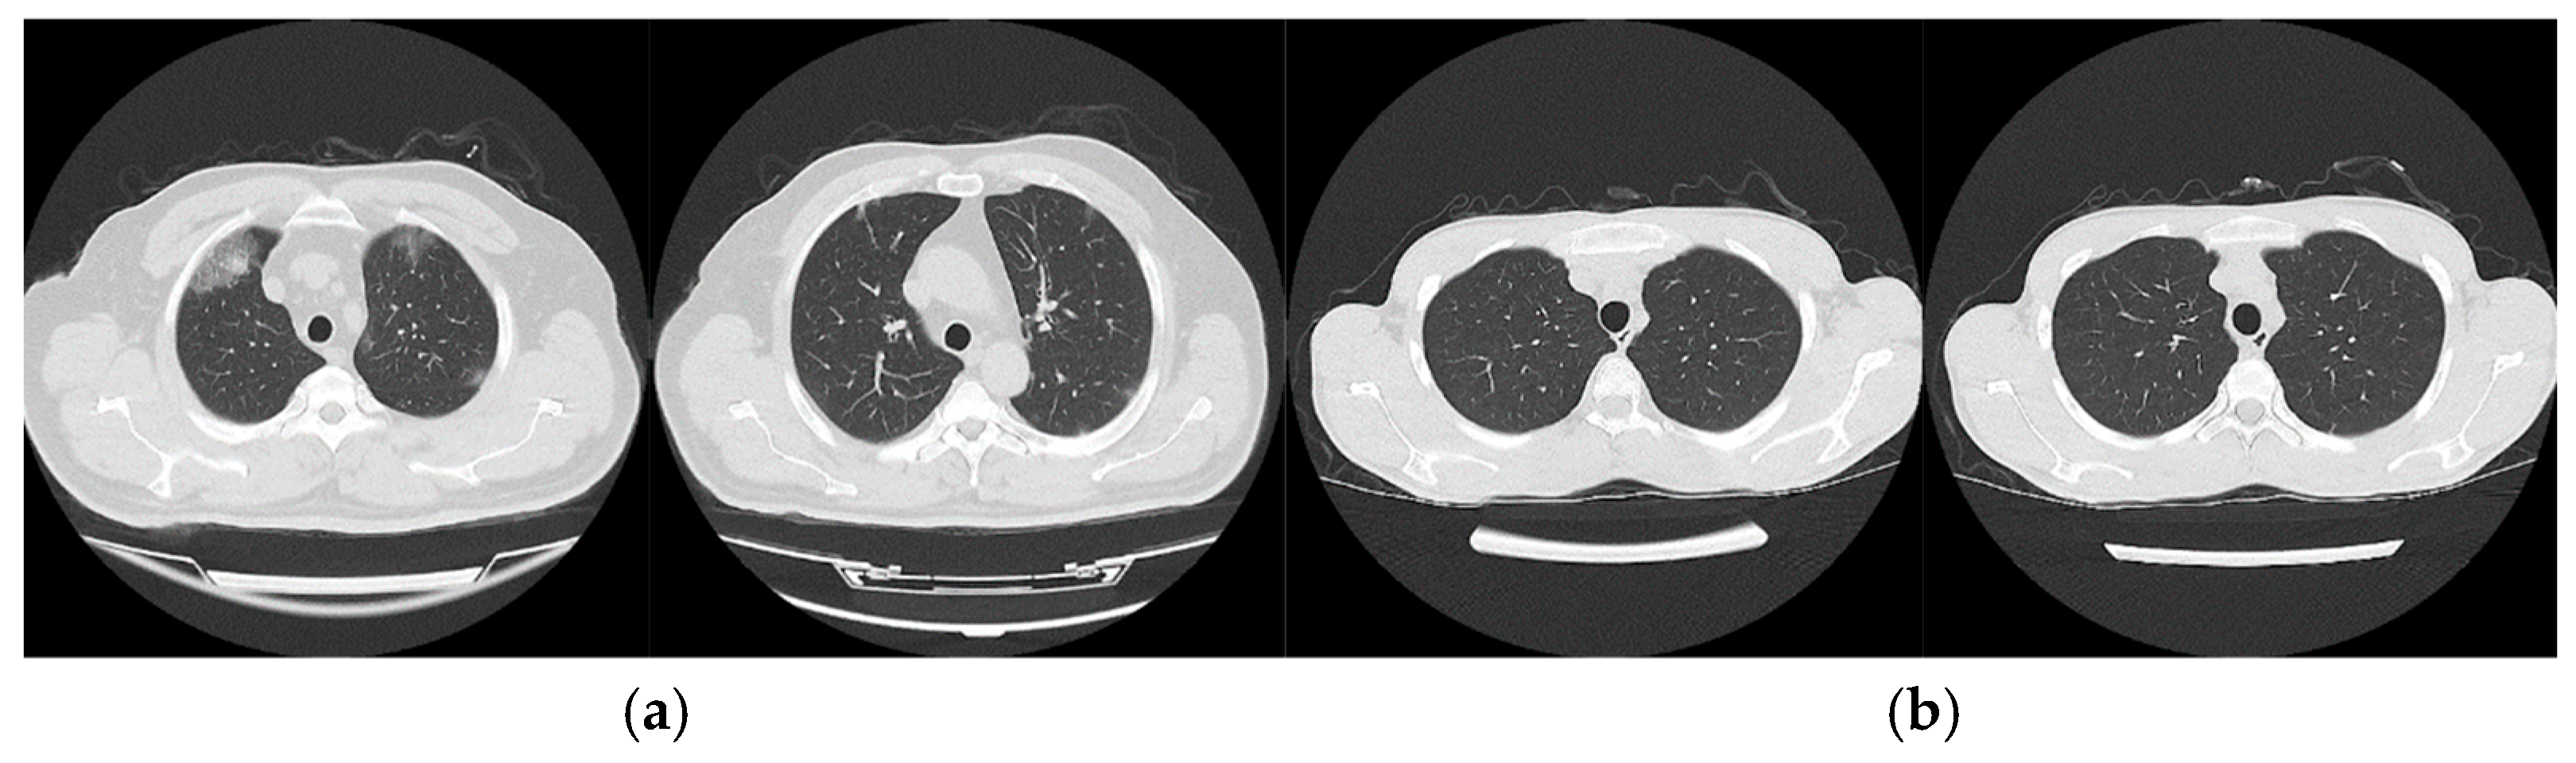

2.2.2. Study Dataset